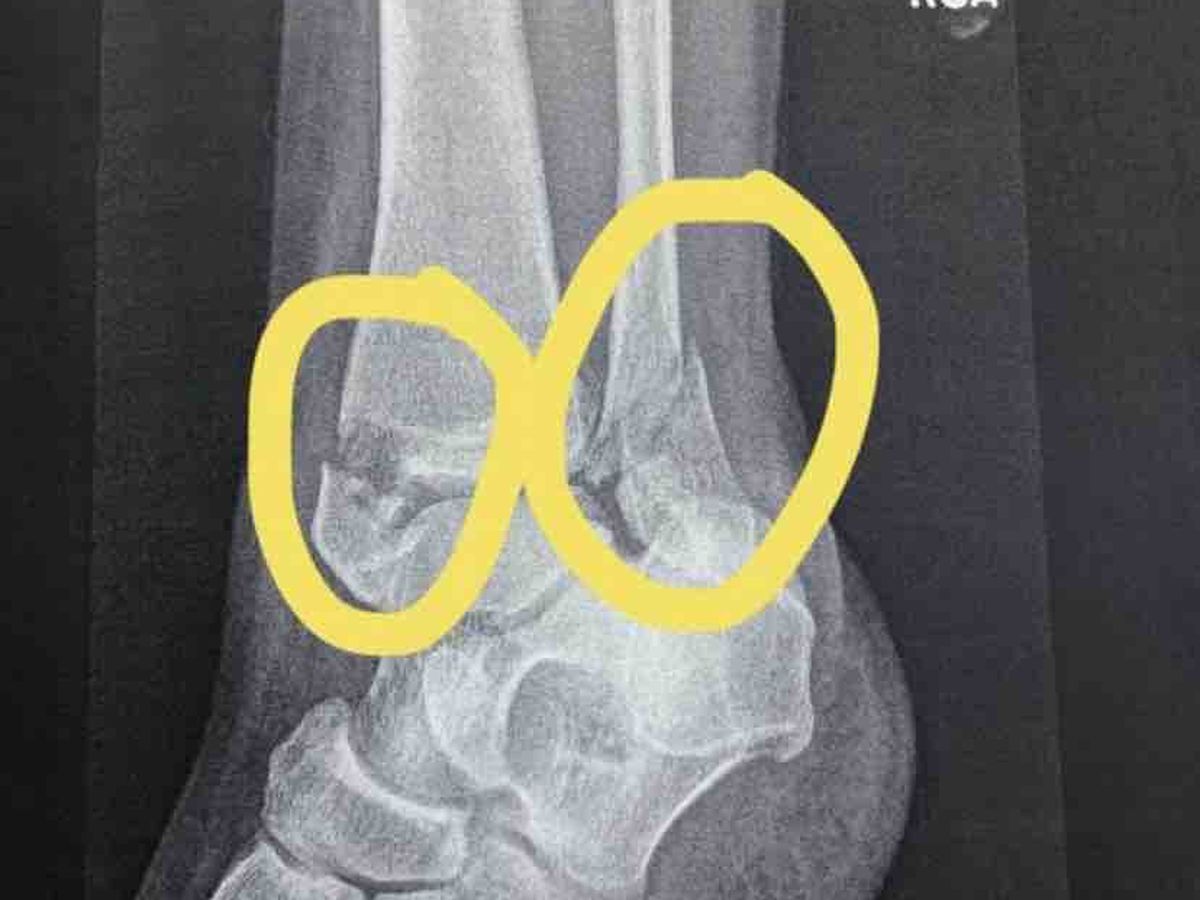

I need to raise enough money to help me get a home. I just need help with 1st last and deposit after that I got it. I clean houses now I use to be a truck driver. But I’m living in my car right now. Now because of the snow and ice I fell and broke my leg in 2 places.